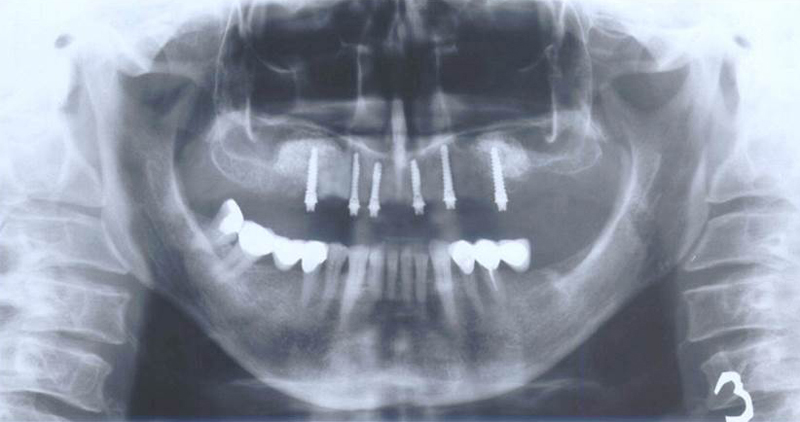

Při ztrátě molárů a premolárů v horní čelisti a jejich náhradě implantáty se často setkáváme s nedostatečnou

vertikální nabídkou kosti pod čelistní dutinou, často doprovázenou i nedostatečnou horizontální nabídkou a sníženou kvalitou kosti (v oblasti 2. premoláru v 50%, v oblasti moláru až v 80% případů nedostatečná kostní nabídka)

Od roku 1985 je tento problém řešen augmentační operací nazývanou

sinus lift.

Jedná se o vyzvednutí membrány, která čelistní dutinu vystýlá, pod vyzvednutou membránou vznikne kapsa, kam se umístí augmentační materiál, do kterého se zavedou implantáty.

Vhojení implantátů se při této operaci prodlužuje na 6-12 měsíců.